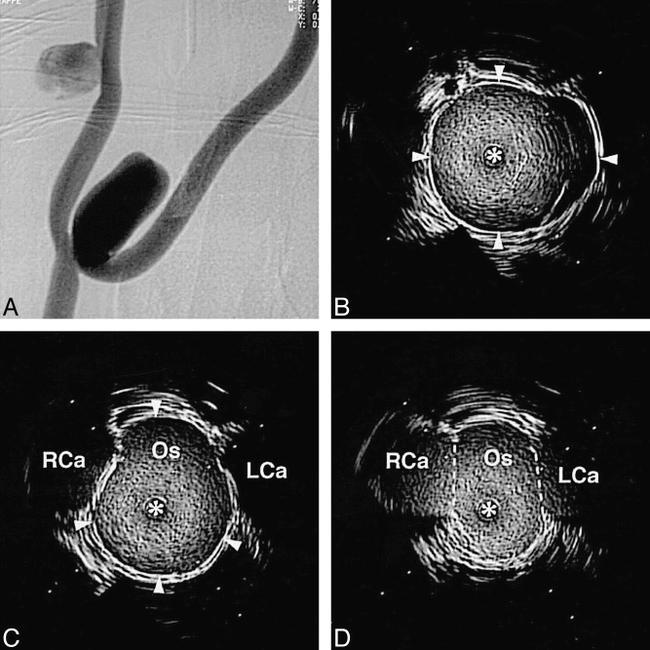

A, Angiogram of experimental aneurysms. The projection is optimized to allow visualization of the bifurcation aneurysm's neck.

B, Intravascular sonogram in the dome of the bifurcation aneurysm (arrowheads define the wall of the aneurysm).

C, Intravascular sonogram at a location just on the aneurysm side of the ostium (Os). The adjacent right and left carotid artery branches (RCa and LCa, respectively) are seen on either side of the aneurysm's wall as hypoechoic regions (arrowheads define the wall of the aneurysm).

D, Intravascular sonogram at the isthmus between the ostium (Os) and adjacent bifurcation branches (dashed lines indicate position at which ostium opens into the bifurcation of the left and right carotid arteries, LCa and RCa, respectively). In the intravascular sonograms the distance between white marker dots is 2 mm, and the intravascular sonographic catheter is defined by an asterisk.